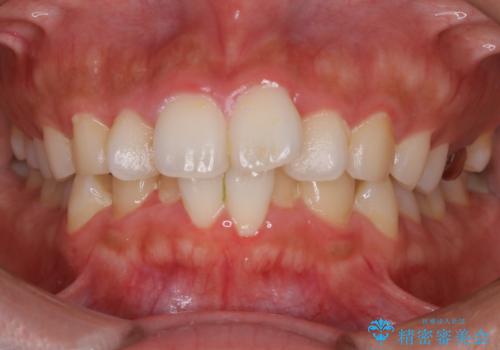

【非抜歯】インビザラインで正しい噛み合わせを

【非抜歯】インビザラインでガタつきと口元を改善!非抜歯でも印象が変わる矯正治療